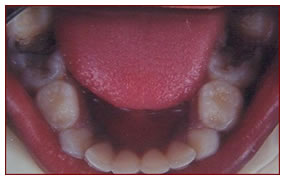

Space Maintainer

The milk teeth guide the permanent set of teeth to erupt in a proper direction. In case of early loss of these teeth by decay or trauma, the space has to be preserved by space maintainers thereby directing the erupting permanent teeth to their normal position.